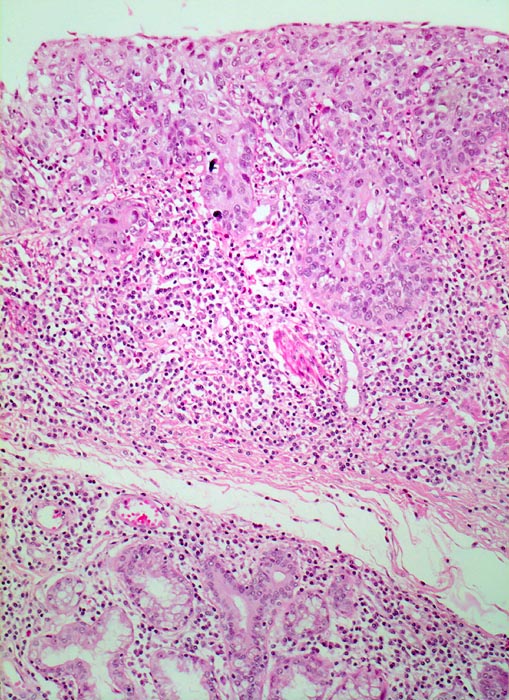

Mikroskopisch zeigen die meisten Plattenepithelkarzinome einen mittleren Differenzierungsgrad und eine wechselnd starke Verhornung. Das fortgeschrittene Karzinom infiltriert angrenzende Strukturen wie den Tracheobronchialbaum, die Aorta und den Nervus recurrens.